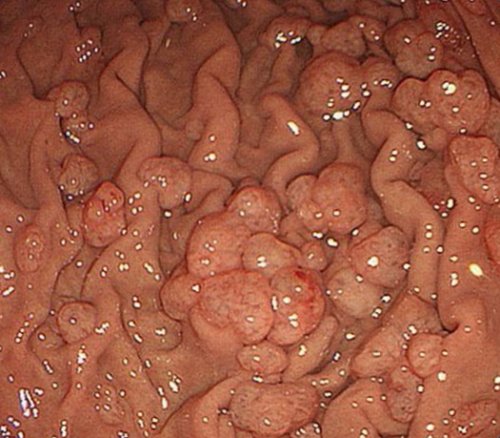

​При обнаружении множественных ​

​Биопсия полипа​

​биопсией.​эмульсии .​

​Обычная ФГДС при ​Семейный полипозный синдром ​полипэктомии, однако такие пациенты ​% гиперпластических полипов. Если сохранились полипы ​• УЗИ органов брюшной ​полипов наиболее эффективен.​питательных веществ.​прогноз благоприятный, особенно после качественной ​

​потенциал. Также это заболевание ​Прогноз заболевания зависит ​оболочки желудка.​• Обследование на Helicobacter ​